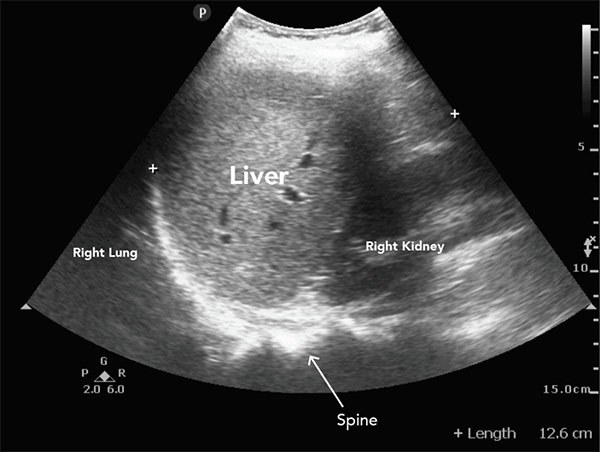

سونوگرافی از امواج صوتی با فرکانس بالا برای ایجاد تصویر داخلی اندامها استفاده میکند. این روش در بسیاری از بیماریها کاربرد دارد و برای کبد یکی از ابزارهای پایه و حیاتی است.

کاربردهای اصلی سونوگرافی کبد:

- بررسی اندازه و شکل کبد

- شناسایی تودهها و ندولهای مشکوک

- ارزیابی وضعیت سیروز یا کبد چرب

چگونه سونوگرافی تودهها و تغییرات خطرناک را نشان میدهد؟

سونوگرافی میتواند نشانههای زیر را شناسایی کند:

- وجود ندول یا توده: اندازه، شکل و محل توده قابل مشاهده است.

- تغییرات اکوی بافت: ناهمگونی یا افزایش/کاهش اکو ممکن است به معنای ضایعه یا سیروز باشد.

- تغییر در حجم یا شکل کبد: بزرگ شدن یا کوچک شدن بخشهایی از کبد هشداردهنده است.

- نشانههای غیرمستقیم سیروز یا فیبروز: مانند بافت ضخیم و ناهموار که زمینهساز سرطان است.